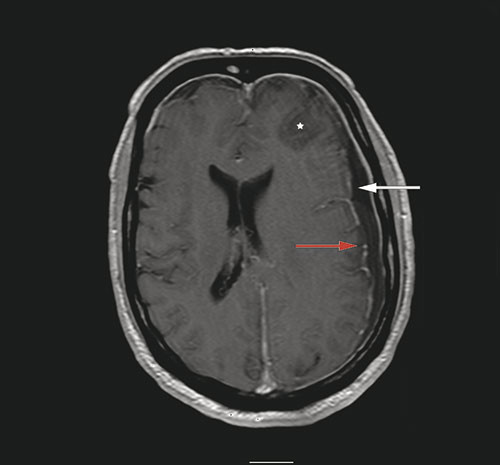

En mann i 60-årsalderen ble innlagt på lokalsykehus etter at han ble funnet konfus og med redusert bevissthet. Han hadde da ifølge komparentopplysninger hatt hodepine i to dager. Ved undersøkelse var han høyfebril (40,5 °C) og nakkestiv. Glasgow Coma Scale ble vurdert til 12. Den nevrologiske undersøkelsen var ellers upåfallende. Cerebral CT tatt med beinvindu i sagittalplan (bilde til venstre) viste fortetning i sinus frontalis og beindefekt (pil) inn mot epiduralrommet. Cerebral MR tatt med T1-vekting etter intravenøs kontrast (bilde til høyre) viste venstresidig subdural væskeeffusjon (hvit pil), kontrastladning i dura (rød pil) og signalforandringer (stjerne) i venstre frontallapp. Spinalvæsken var blakket med hvite blodceller på 2187 · 10⁶/l (normalt 0 – 5) og totalprotein på 1,55 g/l (normalt 0,15 – 0,50). På mistanke om subduralt empyem og cerebritt ble pasienten satt på antibiotika og overflyttet til universitetssykehus. Der ble han operert med kraniotomi og drenasje av empyem samt tetting av beindefekt i os frontale. Dyrkning av puss viste Streptococcus intermedius (Milleri).